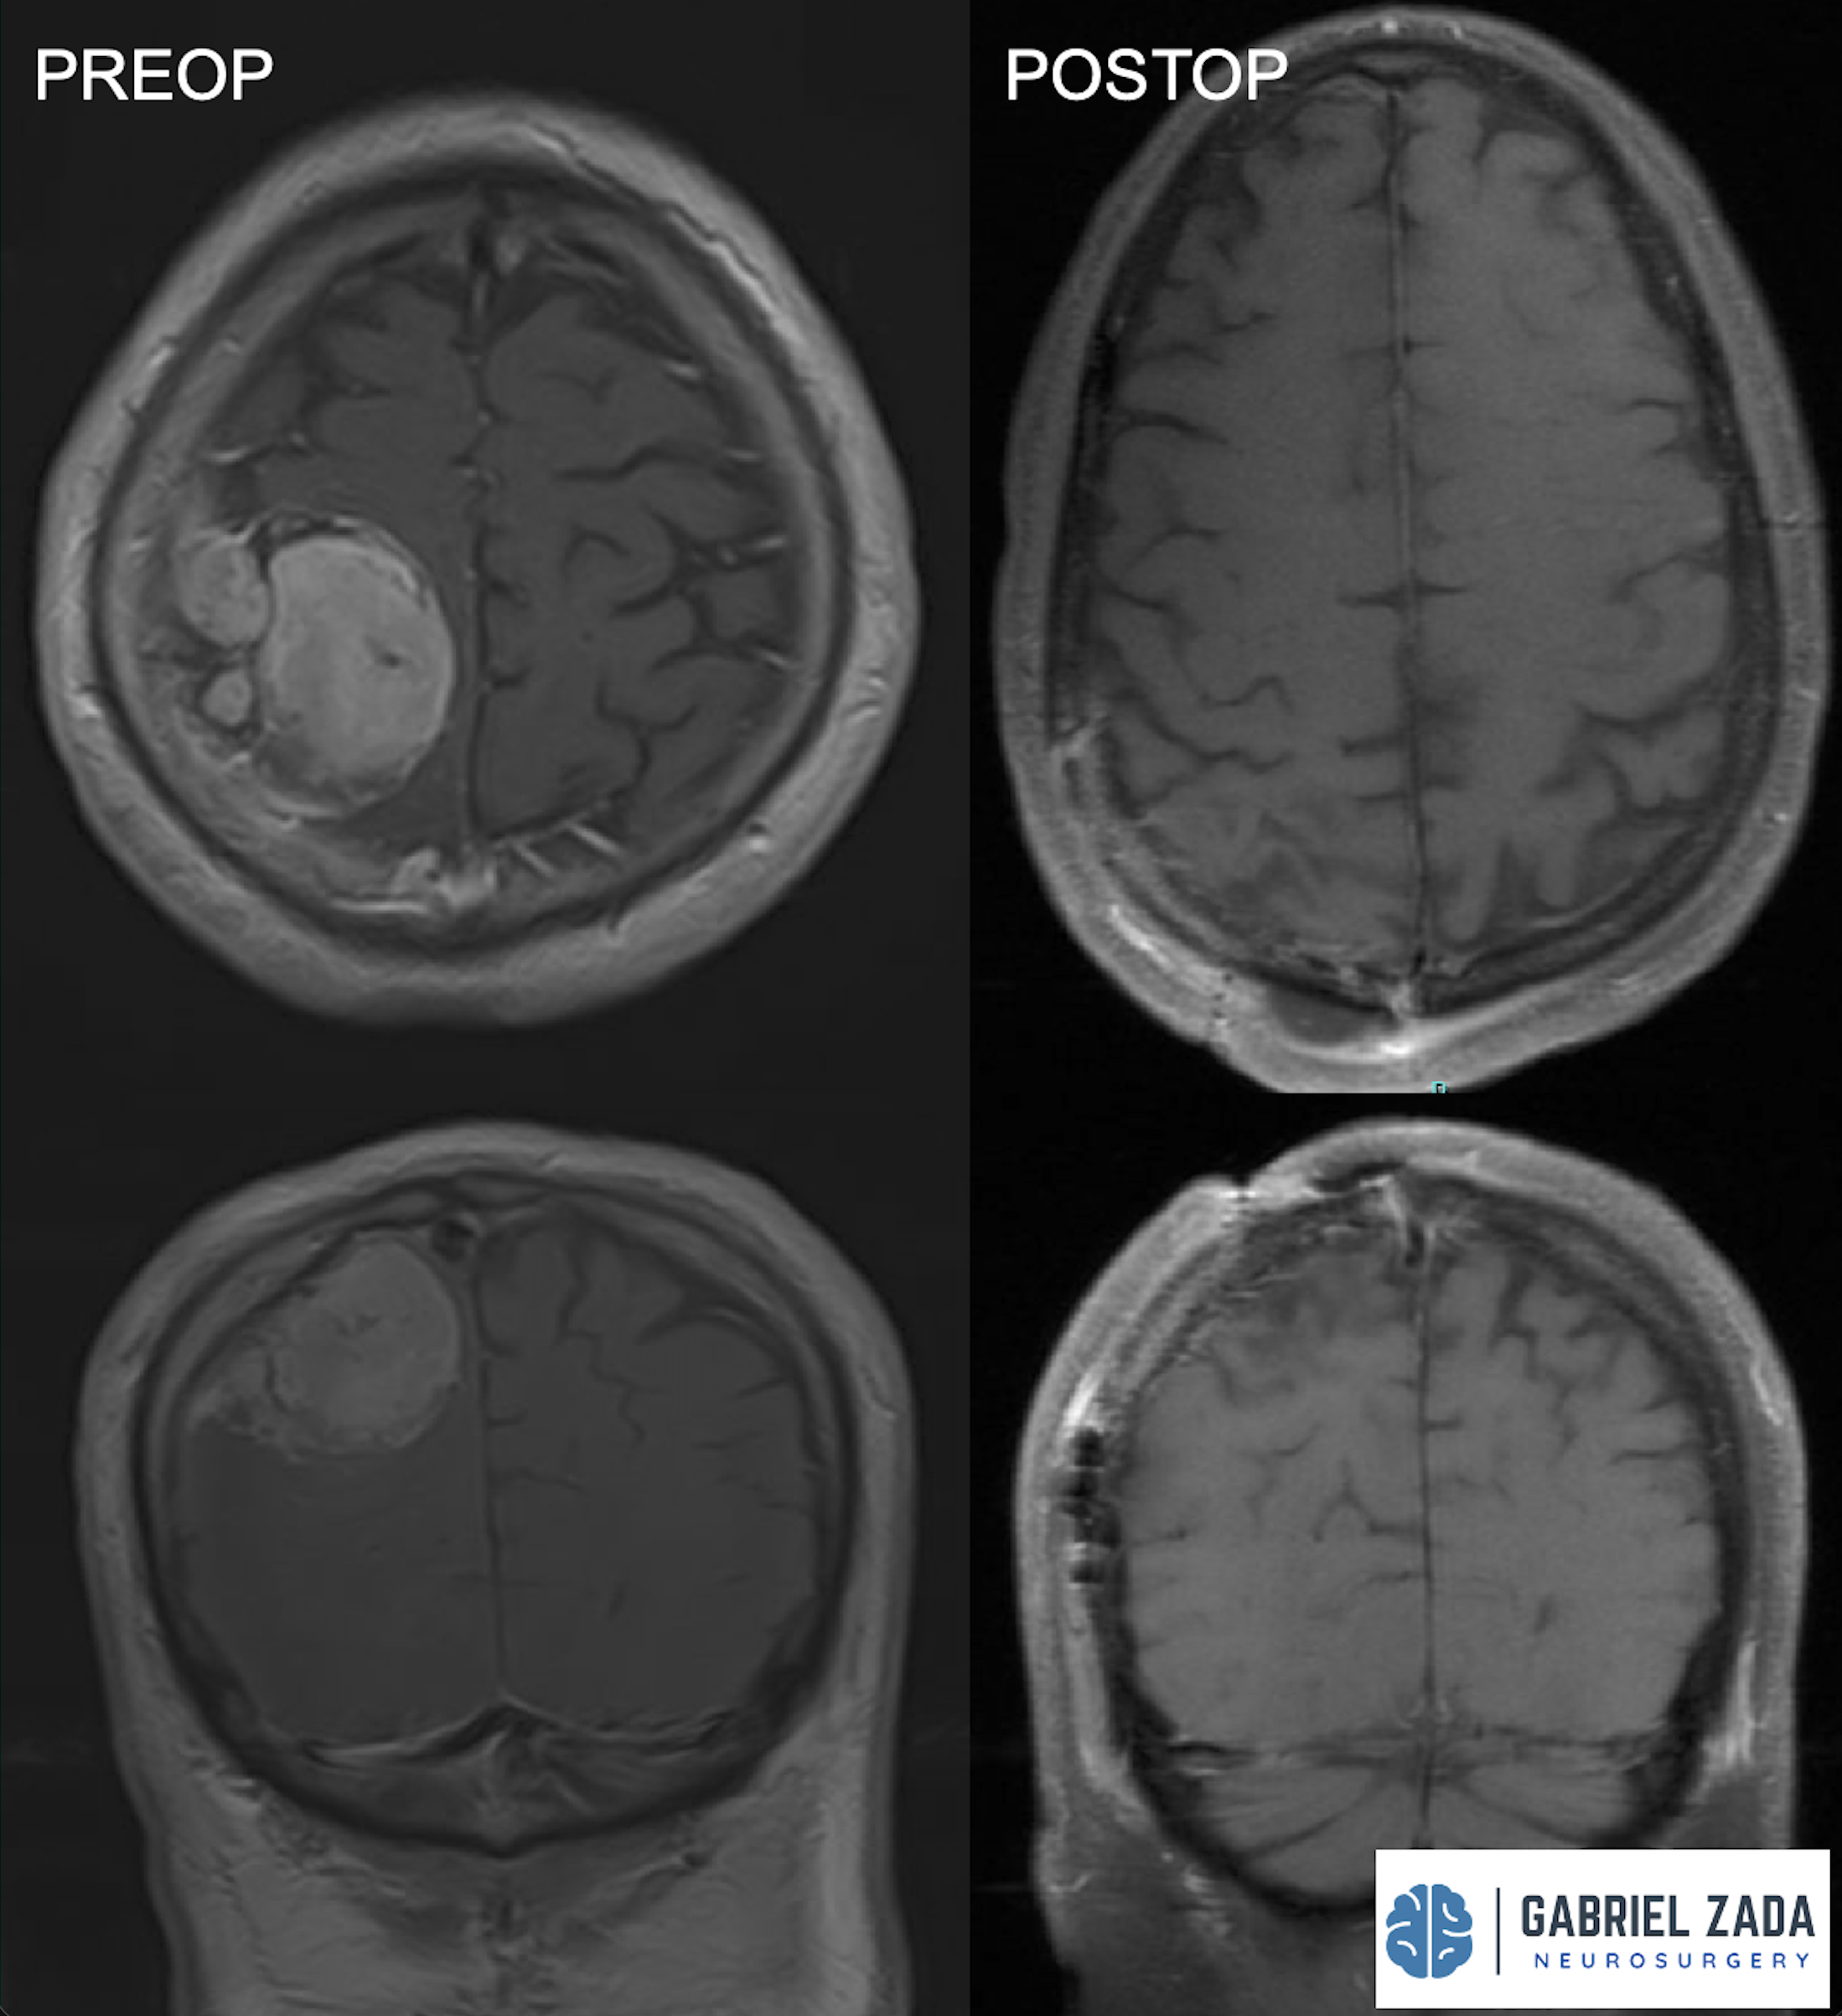

Explore this comprehensive gallery featuring pre‑ and post‑operative imaging of patients with skull‑base tumors treated by Gabriel Zada, MD, MS, FAANS, FACS. These cases highlight Dr. Zada’s expertise in advanced neurosurgical techniques and outcomes.

*Representative cases shown for educational purposes. All images de-identified. Individual results vary.